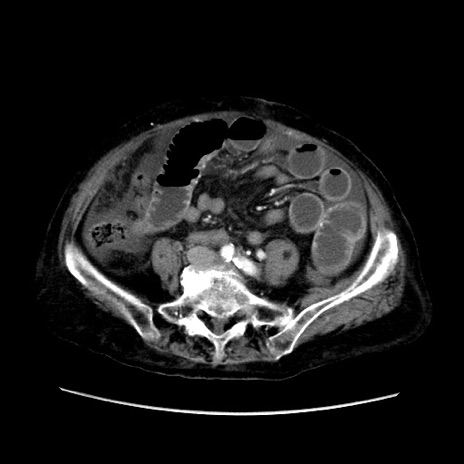

症例31(横断像)

【症例】80歳代 女性

【主訴】腹部膨満感

【現病歴】他院にて肝硬変にてフォロー中。1週間前から便秘、腹部膨満感、臍部腫瘤あり受診となる。

【既往歴】肝硬変

【身体所見】腹部膨隆あり、皮膚変化なし、疼痛なし。

【データ】WBC 4600、CRP 0.25